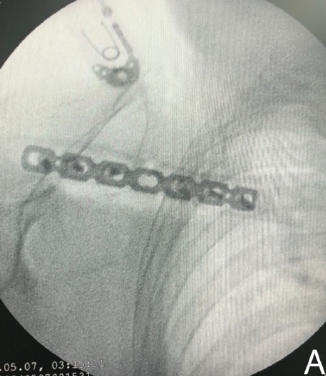

Functional and Radiological Outcomes of Anterior Clavicle Plating in the Treatment of Midshaft Clavicle Fractures – Allman Group 1 Type

Vinoth Karthick Ramanathan , T S Raagul , K V Prem Kumar , Bharath V, Vijayashankar Murugesan V , Thirumal Ranganathan

………………………………p.350-359